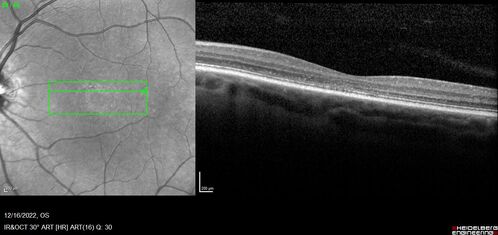

Stargardt Disease - Very Mild - 24 year old

This patient has 3 different ABCA4 mutations. His mother and sister have stargardts and his father has RP. His sisters images are also on Retinagallery.com

Stargardt Sibling - ABCA4 3 mutations